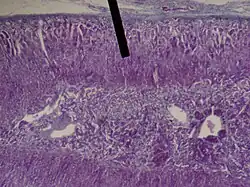

The zona fasciculata (sometimes, fascicular or fasciculate zone) constitutes the middle and also the widest zone of the adrenal cortex, sitting directly beneath the zona glomerulosa. Constituent cells are organized into bundles or "fascicles".

Adrenal gland (zona fasciculata layer).